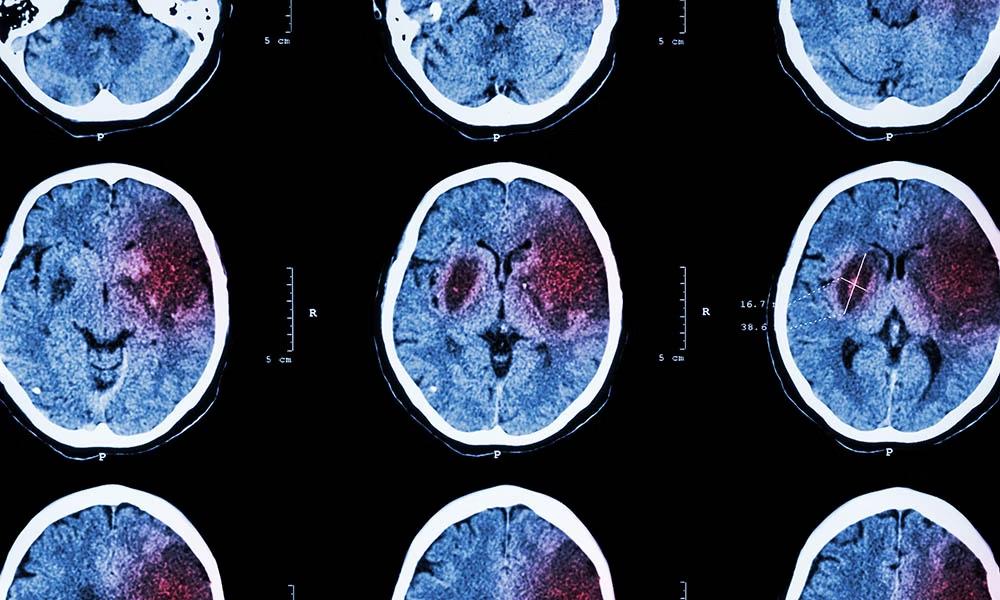

為了確保有針對性的治療,有必要確定患者是否患有血流量減少或腦出血。這通常通過成像技術來完成,例如大腦的計算機斷層掃描 (CT) 和/或磁共振成像 (MRI)。

中風會破壞大腦的血液供應(由于血流量減少或腦出血)。除臨床神經學檢查外,還通過影像技術(CT、MRI)進行診斷。